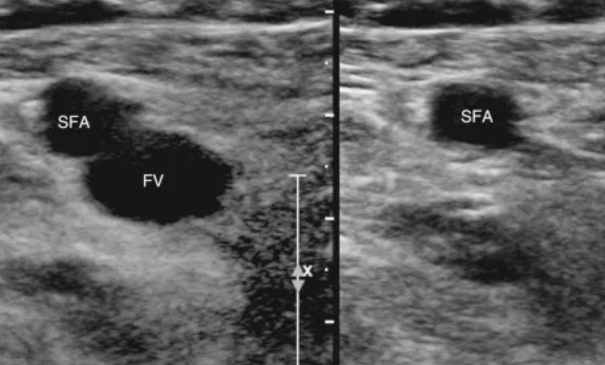

Veine fémorale commune

Veine fémorale superficielle